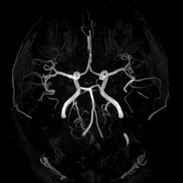

MRI検査

MRIはMagnetic Resonance Imaging (磁気共鳴画像)の略で、強力な磁石の力で体の内部を画像化する装置です。一般撮影検査やX線CT検査などと異なり、放射線を使用しないため被ばくがなく、何回検査をしても体に悪い影響はありません。ただし道路工事をしているような大きな音がしたり、検査室内に金属が持ち込めない等の制限があります。けがの治療などで体内に金属を入れている方は事前にご相談ください。

当院では3.0テスラMRI装置と1.5テスラMRI装置が稼働しています。

- ・脳神経外科領域

- MRIが最も得意とする部位で、頭の血管の描出や脳梗塞、認知症の検査が可能です。予防医学センターでは脳ドックも行っております。